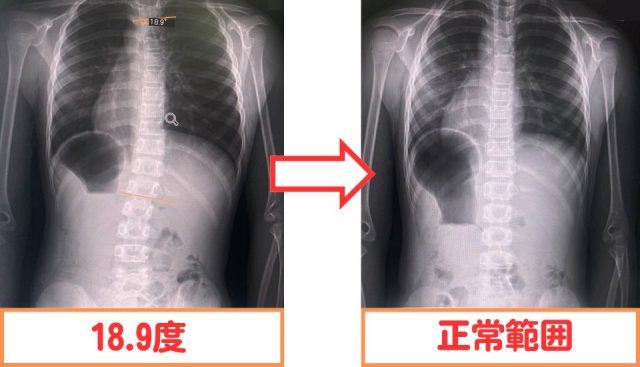

背骨の角度が18.9度から正常範囲に変化しました。

施術計画通りに来ていただき、側弯バランス体操を頑張ったからです。

側弯バランス体操の回数を通常よりも2倍以上頑張ったので結果もでました。